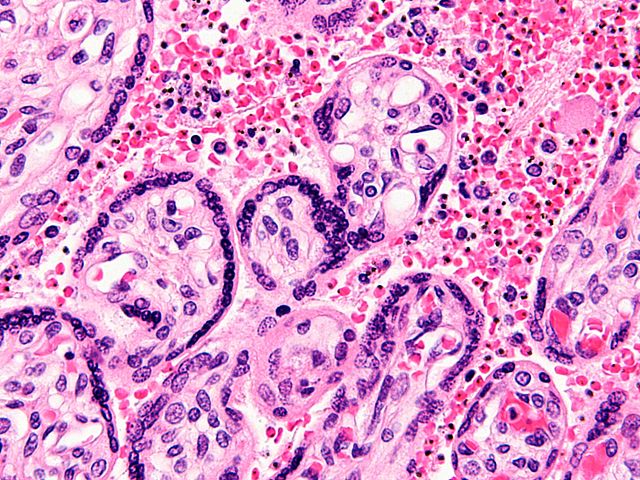

English: Very high magnification micrograph of maternal malaria. Placenta. H&E stain.

The images show organisms within the red blood cells. Related images

Red blood cell infected by malaria.

Red blood cell infected by malaria.

Chorionic villus.

Syncytiotrophoblast.

Fetal red blood cell.